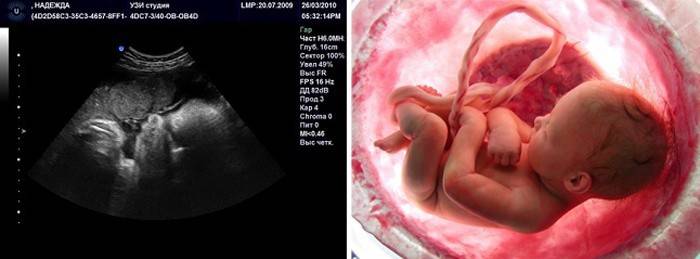

Exame de ultra-som (Uzi)

Neste período, todos os ultrassons planejados foram concluídos há muito tempo e estudos adicionais são realizados apenas em indicações especiais e na prescrição de um médico. Um ultra-som ou estudo Doppler é indicado para monitorar a condição do bebê ou excluir seu sofrimento (hipóxia, patologias). Usando ultra-som, o médico pode avaliar a condição e estrutura da placenta, seu grau de maturidade e a presença de calcificações na mesma. Isto indicará quão bem a placenta lida com seus deveres.Se a placenta é muito antiga, pode não ser capaz de lidar com suas funções, e o feto experimentará hipóxia. O ultrassom determinará o período e o peso e a altura estimados do feto e a condição de seus órgãos internos.

O cordão umbilical também parece, sua localização e comprimento, se há um colo fetal entrelaçado com ele. Se tal for revelado, durante o parto, um benefício especial será mostrado, com a ajuda de que as alças do cordão umbilical são removidas do colo fetal e evitam que o sufocamento se desenvolva. Por ultra-som, o útero também é avaliado - a condição de suas paredes e pescoço, sua prontidão para o parto. É possível realizar ultrassonografia 3D, mas já é impossível ver todo o miolo, suas dimensões são muito grandes.